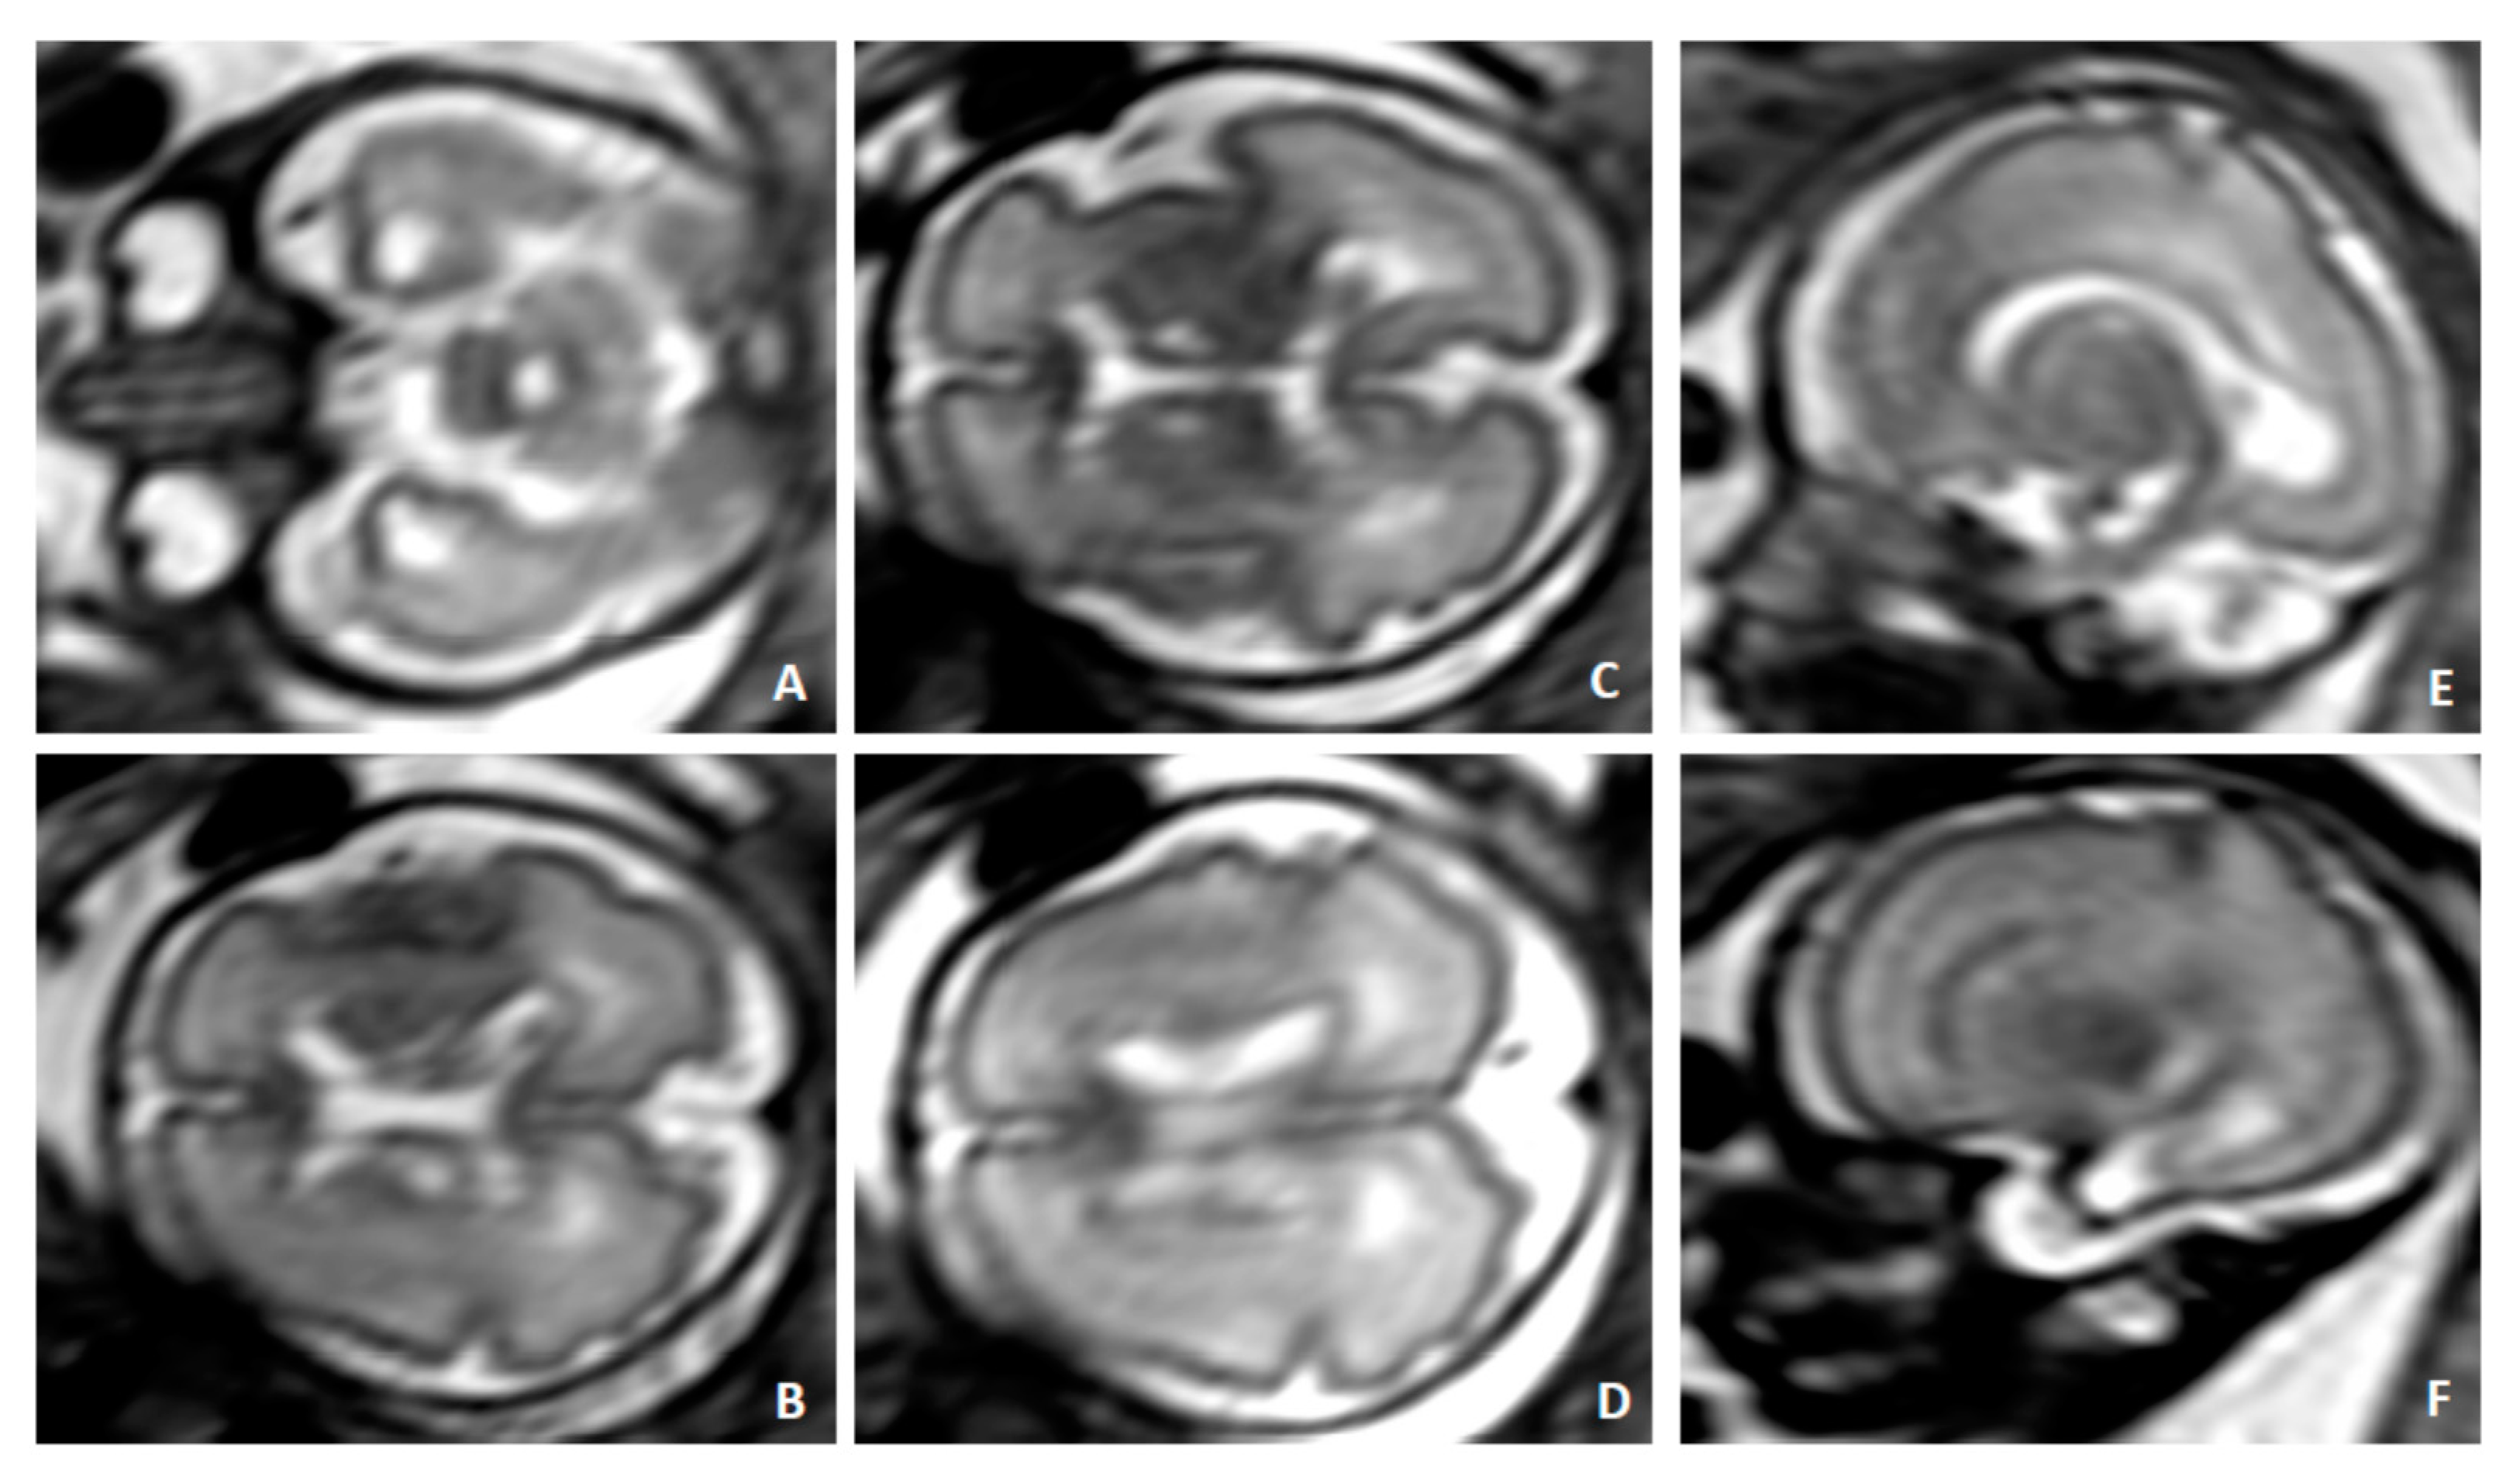

2. Case Presentation